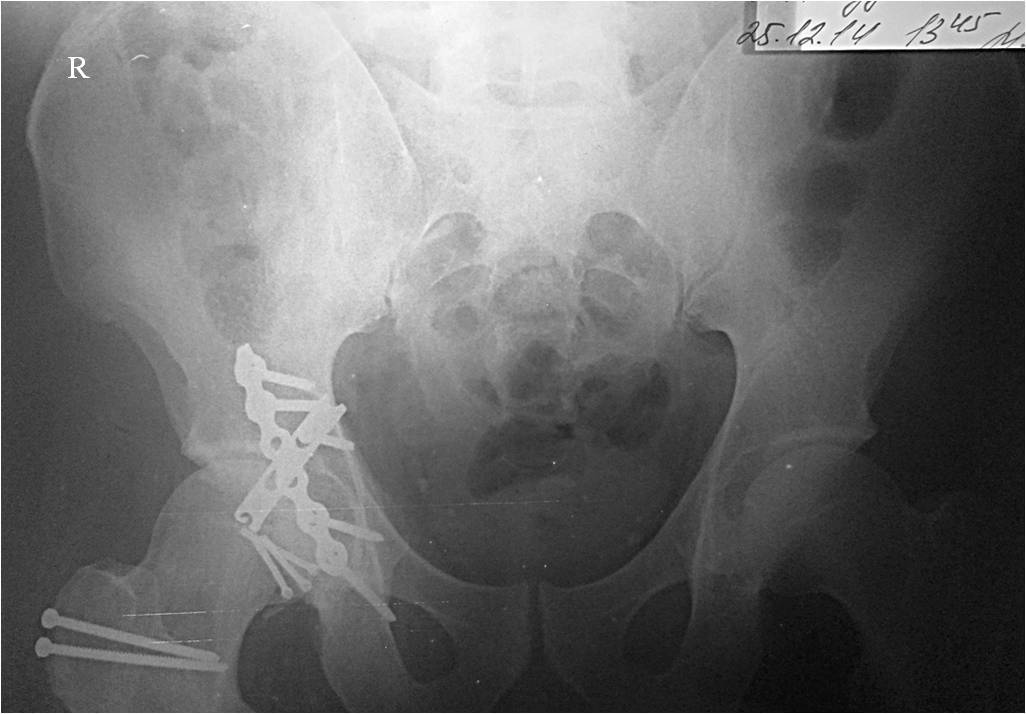

Мужчина, 46 лет, пострадал в результате ДТП (водитель). Удар пришелся через согнутое правое колено об приборную панель, что привело к заднему вывиху головки бедра. При госпитализации кроме вывиха бедра диагностирован перелом нижнего сегмента головки бедра и закрытый перелом с/3 правого плеча (АО 12-В2).

При поступлении выполнено закрытое вправление головки бедра, налажено скелетное вытяжение. Контрольный рентген показал разницу в ширине суставных щелей в сравнении с неповрежденной стороной. Сделали КТ, которое подтвердило наличие внутрисуставного фрагмента задней стенки вертлужной впадины и перелом нижне-медиального сегмента головки со смещением (Pipkin IV).

Через 12 дней выполнен остеосинтез головки 3-мя самокомпрессирующими винтами Герберта. Доступ Kocher-Langenbeck с флип-остеотомией большого вертела и задним хирургическим вывихом головки бедра. Интерпонирующий внутрисуставной фрагмент представлял собой лабрум с тонкой костной пластинкой от заднего края впадины. Фрагмент извлечен и фиксирован техникой spring-plate.